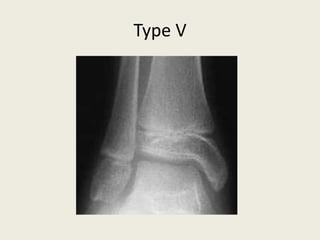

• A longitudinal compression injury of the physis.

• There is no visible fracture but the growth plate is

crushed and this may result in growth arrest.

• This injury is rare and difficult to see on x-ray.

• Compression fracture or crushing of the growth plate.

• These injuries are almost always diagnosed retrospectively, when a growth

arrest has occurred.

TypeV

Type V